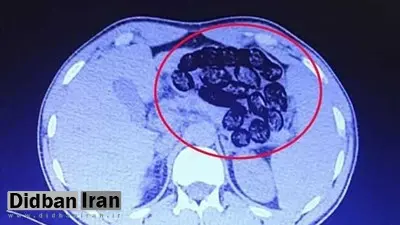

در ادامه این اطلاعیه آمده: بر اساس توضیحات مأمور همراه، این فرد پیش از ورود به بیمارستان، اقدام به بلع چندین بسته محتوی مواد مخدر کرده بود و در تصویربرداری‌های انجام‌شده، مشخص شد تعداد قابل‌توجهی بسته درون معده و روده‌های کوچک و بزرگ او شناسایی شد.

بعد از عمل جراحی مشخص شد این فرد میانسال ۹۰ بسته مواد مخدر را بلعیده است.